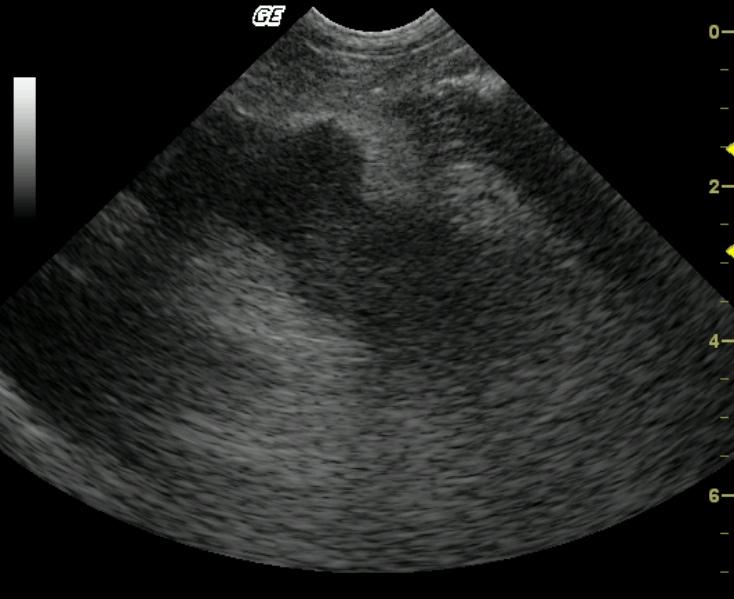

This 6-year-old Maltese presented for diarrhea, poor appetite, and lethargy immediately prior to the sonogram with a history of acute vomiting 2 weeks prior that had resolved without intervention. The patient also presented concurrently with acute anal sacculitis and dermal hot spots. Outpatient therapy with antibiotics proved mildly effective. CBC and blood chemistry analysis demonstrated a normal complete blood count and moderately elevated amylase, moderately elevated lipase, and moderately elevated SAP. Mild hypoalbuminemia was also present initially. A second analysis revealed similar values regarding amylase, lipase, and SAP with new moderately elevated cholesterol and moderately elevated triglycerides and moderate hypoalbuminemia.